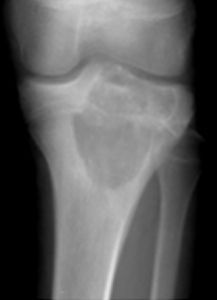

Symptoms of chondroblastoma may vary depending on the location of the tumor. The most common symptoms include: Pain in the knee, hip, and shoulder joint that may be slight or moderate and may be felt for months or years Withered or shrunken appearance of the muscle near the affected bone Joint stiffness Joint swelling A limp if the tumor is in the leg The symptoms may look like other medical conditions or problems. Always talk with your healthcare provider for a diagnosis.